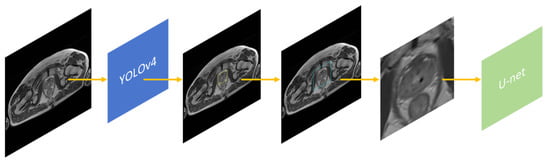

The YOLOv4 is an intermediate stage for segmentation carried out by the U-Net neural network. In this paper, the purpose of YOLOv4 is to filter areas where prostate cancer can initially be found. Figure 4 presents the created research workflow.

Figure 4.

Post-processing workflow for prostate detection image. Legend starting from left: input image in N × N size; YOLOv4 convolutional neural network; prostate detection output with yellow bounding box; prostate detection output with enlarged turquoise bounding box (15 px padding); cropped prostate detection output and resized into 256 × 256 px as U-Net input; U-Net convolutional neural network to segment prostate.

The predicted prostate image was subjected to additional processing, as presented in Figure 7. The object detected by the YOLOv4 with the bounding box label enabled further image processing. Subsequently, an additional 15 px of padding was added. The framed part of the image had been cut out and resized to 256 × 256 pixels. The cropped image was prepared in order to become the input for the U-Net Segmentation Neural Network. The complete post-processing workflow is visualized in Figure 4.